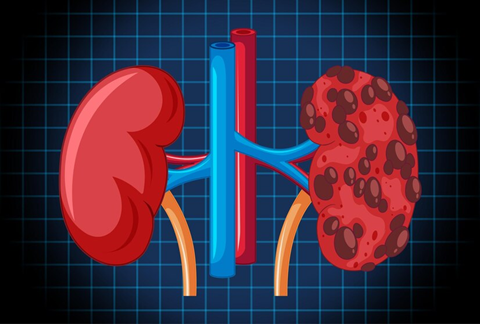

Polycystic Kidney Disease: What to Know About This Silent Disorder

What Is Polycystic Kidney Disease? PKD is a genetic condition where cysts, which are fluid-filled sacs, develop in the kidneys.